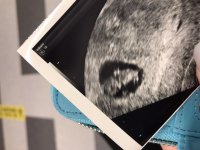

Er vel kun pga sommerferien jeg har ventet så lengeda jeg var innom legen i vinter og sa vi skulle prøve etter mensen i mai, så sa han at han gleda seg på våre vegne, og til jeg skulle på første kontroll rundt uke 8 og se med UL. Meeeeen så kom jo min uke 8 midt i fellesferien

hjertet banket og vi fikk til og med et lite hopp. Målte helt riktig til hvor langt jeg var